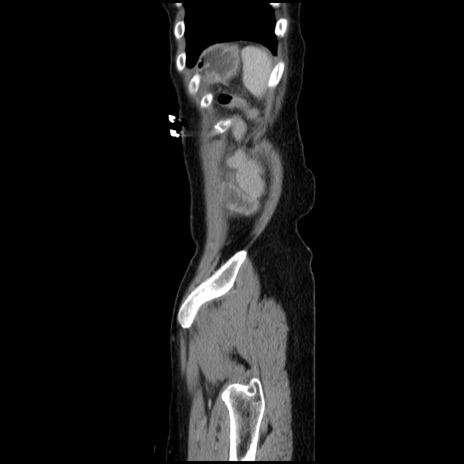

冠状断像